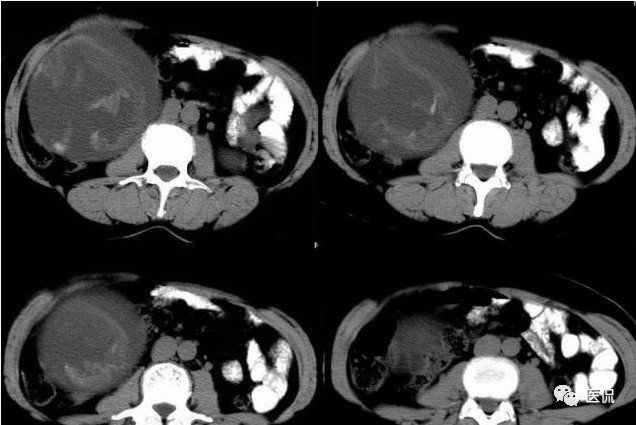

影像特点

腹腔内残留的纱布在人体内引起渗出或液化坏死并纤维包裹形成异物性脓肿(纱布瘤)。纱布瘤的影像特点:圆形或卵圆形肿块,较大,有完整包膜,薄壁,较少的情况下为厚壁,边界较完整,增强后薄膜可以持续强化。不同时期的纱布瘤可以有不同表现:早期(10个月或半年内)多表现为蜂窝状;2~5年内一般表现为囊性飘带状;10~20年之后则为实性软组织密度,包膜钙化呈钙化网状结构。手术过程中残留在人体内的医用纱布所形成的肿瘤样病变。

纱布团遗留腹腔后,首先由大网膜及邻近肠管将其紧密粘连并包裹,自肠管与纱布团粘连处开始逐渐向周围扩展产生纤维结缔组织包膜直至完全包住纱布团,该包膜血管丰富,充血明显,随时间延长逐渐向纱布团网眼内生长,使包膜逐渐增厚。机体还通过在包膜内产生大量异物巨细胞来围歼异物纱线,使包膜内侧形成脓肿。当包膜完全形成后,肠管与纱布团的粘连变的疏松,此时纱布团具有了一定的活动度。

腹腔内遗留纱布团的影像学表现,以B超较具特征性,其主要表现为:腹腔或盆腔内特殊率减的黑色包块,后方伴有扇形衰减的声影,上窄下宽,好似一“黑色大布”,早期包块内含有不规则光团或光点,随时间延长有缩小或消失,为纱布团内气体。CT的优势在于早期常表现为软组织密度的肿块,其内可见多少不等的气泡,随时间的延长气泡逐渐被吸收减少至消失,增强扫描可见包膜不同程度强化而内容物无强化。熟悉其影像学表现,可在术前作出明确诊断。